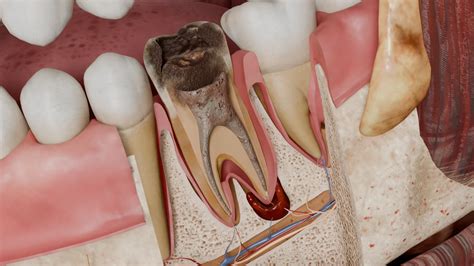

Teeth are complex structures composed of several layers, each serving a specific purpose. The outermost layer is the enamel, which is the hardest substance in the human body. Beneath the enamel lies the dentin, a layer that provides support and structure. At the center of the tooth is the pulp chamber, which contains the dental pulp.

Dental pulp is a soft tissue found in the center of the tooth, within the pulp chamber. It consists of nerves, blood vessels, and connective tissue. The pulp is crucial for the development and health of the tooth. It provides nutrients and sensory information to the tooth, enabling it to respond to stimuli such as heat, cold, and pressure.

Cavities occur when bacteria in the mouth produce acids that erode the enamel and dentin, eventually reaching the pulp. If the decay is not treated, it can cause inflammation and infection of the pulp, leading to severe pain and the need for a root canal treatment.